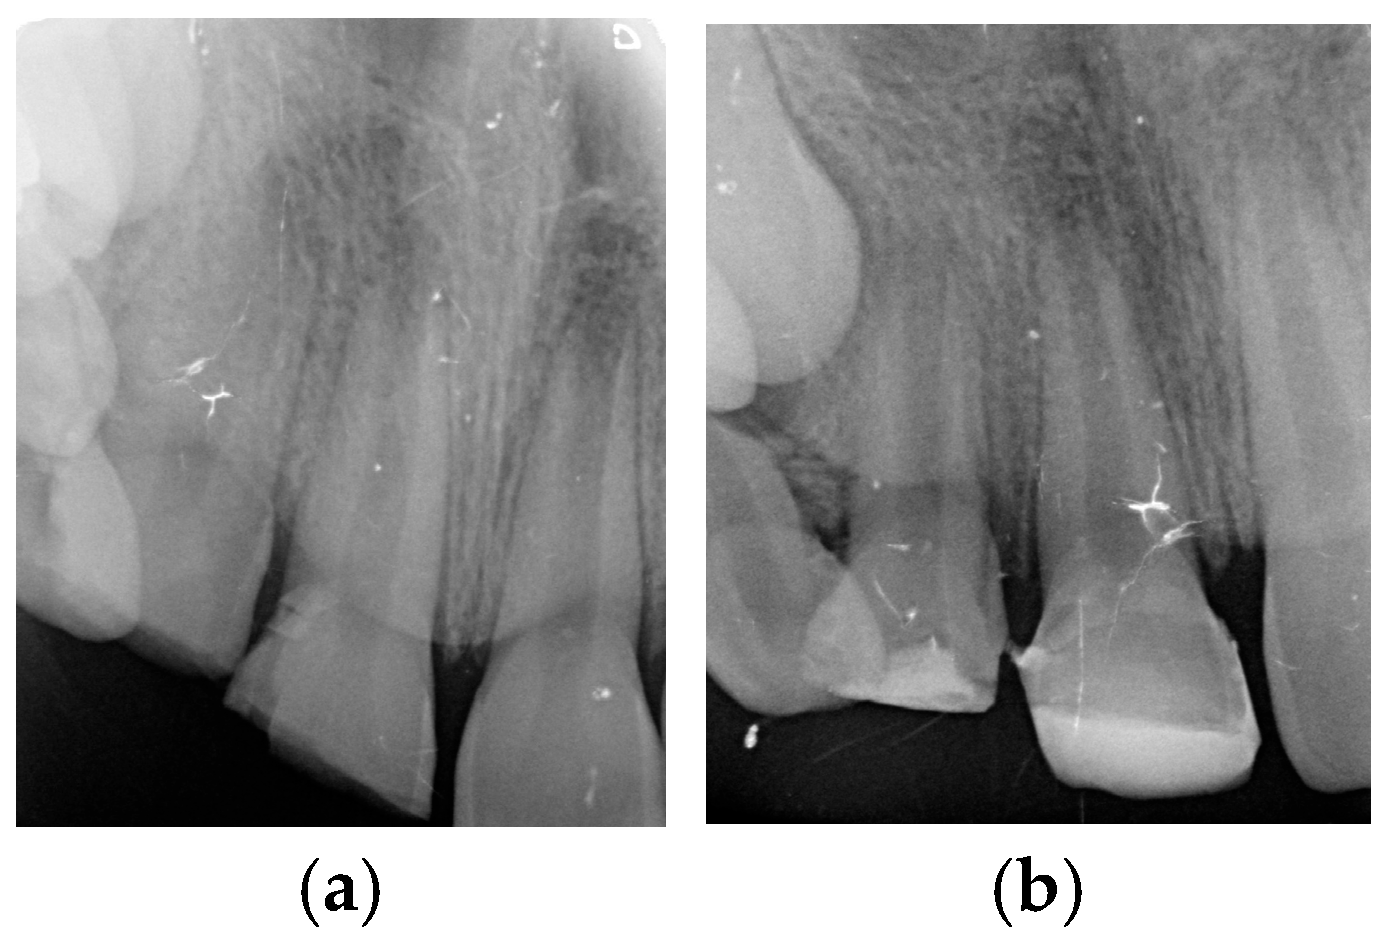

| Case 1 | 12 | 17% EDTA NaOCl | TAP | MTA | 3.7 mm | 2.2 mm | Calcified apical barrier |

| Case 2 | 11/21 | 17% EDTA NaOCl | Ca(OH)2 | BIODENTINE® | 3.1 mm/2.8 mm | 2.3 mm/2 mm | Calcified apical barrier |